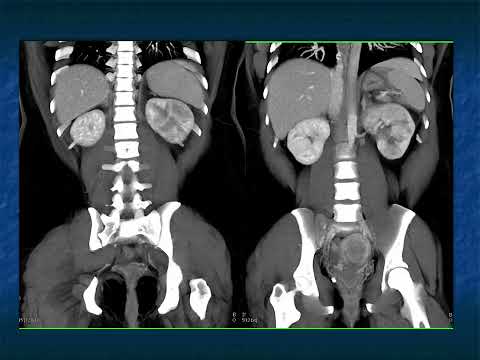

CT appearances and findings are the primary objective for radiologists to determine the accurate diagnosis during reading scans while considering patients' clinical presentation.

This section provides CT appearance for major organ systems and their common malignancies for the radiologists' convenient access that are supplemented with related pearls and lectures from CTisus to enhance radiologists' knowledge for each pathology.

View moreAccess over 322,000 CT Scans and the diagnosis that is identified for each case. The case studies range from CT Scans, MRI, and X-Rays, and are organized by anatomical region: Cardiac, Pancreas, Pediatric, Vascular, Gastrointestinal and more.

Our popular series from social media is now available here on CTisus.com. Each case presents 2 CT images. You can take your time evaluating them and making the call on the diagnosis. When you are ready, you can watch a discussion explaining the case and diagnosis in detail by Dr. Fishman.